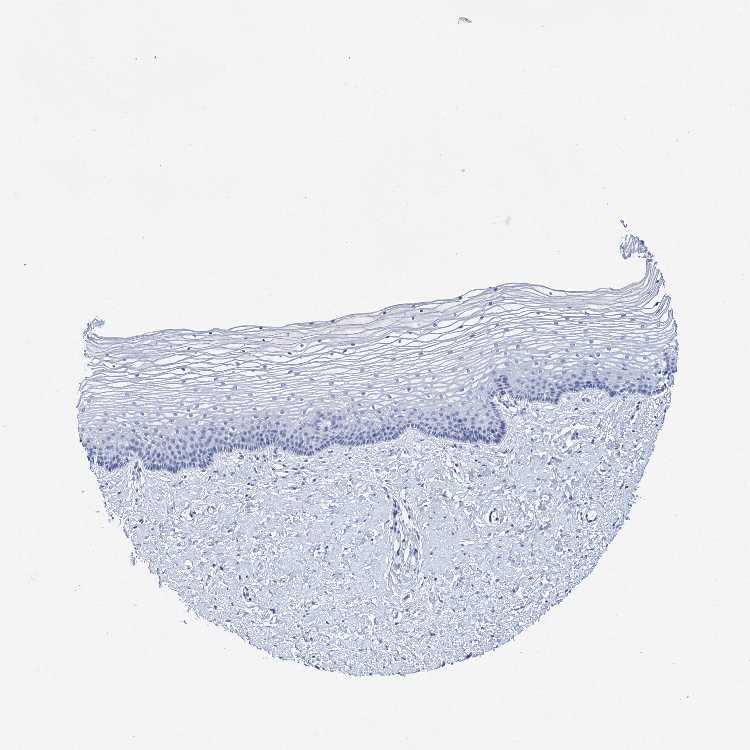

TISSUE PRIMARY DATA VAGINA Show tissue menu

VAGINA - Antibody stainingi

Antibody staining in the annotated cell types in the current human tissue is reported as not detected, low, medium, or high, based on conventional immunohistochemistry profiling in selected tissues. This score is based on the combination of the staining intensity and fraction of stained cells.

Each image is clickable and will lead to virtual microscopy that enables deeper exploration of all samples and also displays staining intensity scores, fraction scores and subcellular localization as well as patient and tissue information for each sample.

Antibody HPA038828

Squamous epithelial cells Not detected